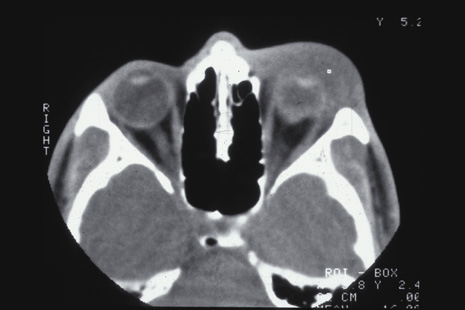

The hallmarks of scleral rupture are severe reduction in visual acuity, an afferent pupillary defect, hypotony (although a normal intraocular pressure does not rule out a small rupture), an abnormally deep anterior chamber, decreased ocular ductions, severe subconjunctival edema (Fig. 24), hyphema, and vitreous hemorrhage.92 The diagnosis can rarely be confirmed by ophthalmoscopy because severe vitreous hemorrhage, hyphema, or both nearly always accompany scleral rupture. Ultrasonography and computed tomography (CT) scanning may be helpful. Both show a shrunken globe. In addition, the CT scan shows subconjunctival edema (Fig. 25). In eyes in which the anterior chamber depth cannot be seen because hyphema, ultrasonography and CT scanning often show a deepened chamber. CT scanning is also useful in identifying any intraocular foreign bodies.

Fig. 25. Computed tomography of a patient with a ruptured globe demonstrates severe subconjunctival edema and a collapsed globe.